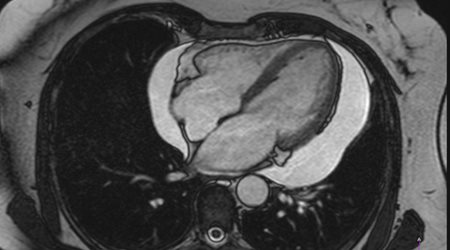

التهاب و عفونت قلب